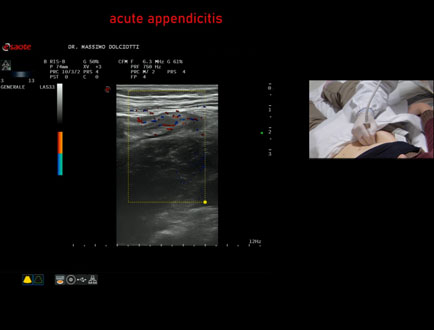

Data inserimento: 15/01/2026

Ecografia del: 07/01/2025

Strumento: Esaote MyLab Eight

Sonda: Lineare Multifrequenza 3-13 MHz

Età Paziente: F 39 anni

Motivazione dell'esame: dolori addominali epiastrici da 2 gg, anche notturni, non nausea, non vomito, non diarrea, non febbre, diuresi normale, nicturia saltuariamente.

Commento all'esame: le immagini ed il video documentano, in sede ileo-cecale, appendice di spessore aumentato (11 mm - V.N. inferiore a 6 mm). Gli elementi ecografici segnalati orientano per appendicite acuta.

Conclusioni: appendicite acuta (acute appendicitis).

In collaborazione: Dr.ssa Marica Manfredi - Ancona, Dr. Ilir Qose - Ancona

Presentazione: Dr. Massimo Dolciotti - Ancona

Elaborazione digitale: Andrea Dini - Ancona